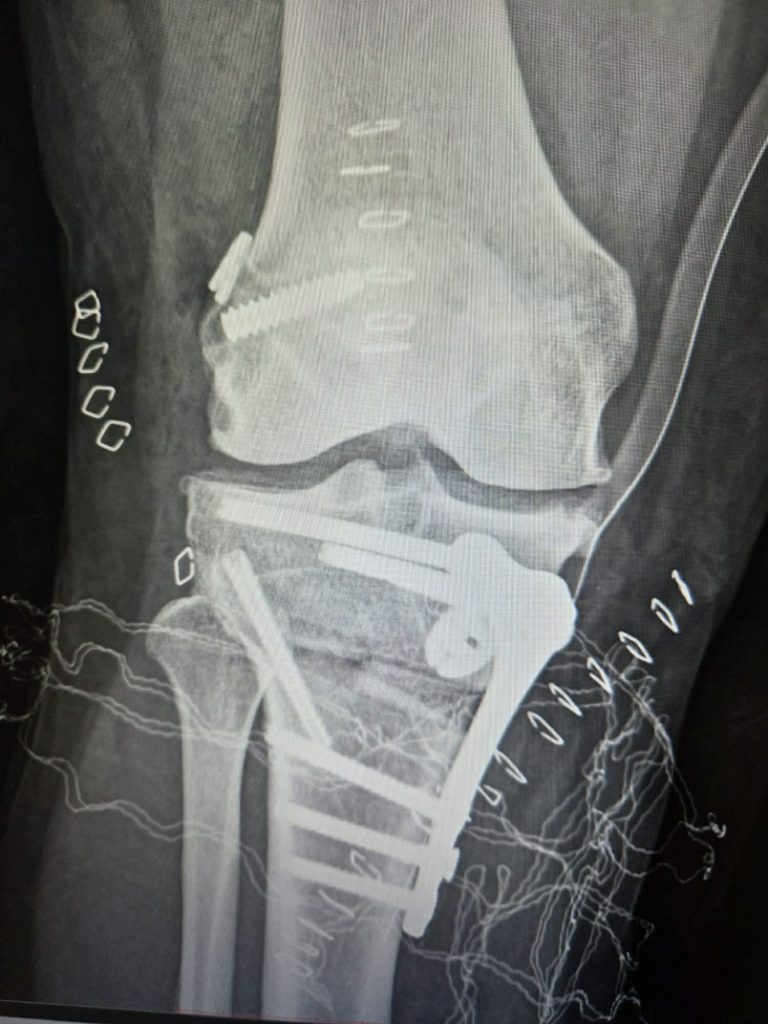

To nie była standardowa operacja. Aby ją precyzyjnie wykonać konieczne było stworzenie modelu 3D. Bez PSI (specyficznego dla danego pacjenta instrumentarium) nie byłoby to możliwe. Bazując na nim zespół medyków na czele z lek. Mateuszem Jobem, kierującym oddziałem Chirurgii Urazowo-Ortopedycznej w Bocheńskim Szpitalu, tak przyciął kość i zrekonstruował więzadło krzyżowe, że problem niestabilności kolana został wyeliminowany raz na zawsze.

Aby wyeliminować problem konieczne było stworzenie modelu 3D i precyzyjne przemodelowanie kości piszczelowej. Z pomocą przyszedł Jakub Piękoś inżynier medyczny z Warszawy, który zaprojektował komputerowo i precyzyjnie wymierzył przycięcie kości w kilku płaszczyznach. Stworzony model 3D posłużył lekarzom jako przewodnik śródoperacyjny.

Musieliśmy przyciąć kość w takich kierunkach, aby po wprowadzeniu płytki, zrekonstruowane więzadło zostało utrzymane nawet w przypadku wykonywania ruchów skrętnych.